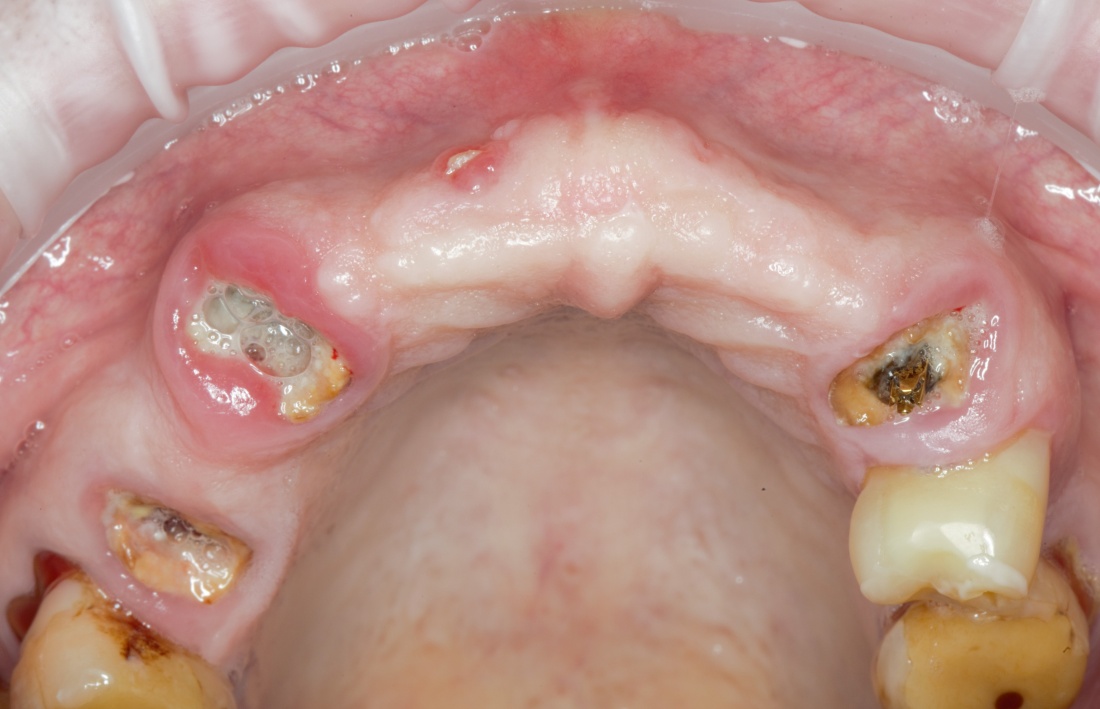

В общем, так и получилось. Уж не помню, почему я наобещал пациентке, что мы поставим ей имплантаты одновременно с остеопластикой. Но я наобещал. И, когда увидел клиническую картину в полости рта:

у меня появились серьезные сомнения, смогу ли я выполнить своё обещание. Вот только не спрашивай меня «Вот чо, сложно было по КЛКТ посмотреть?». Я же не спрашиваю тебя, где ты был в 2013 году, и сделал ли ты домашку. Но, в целом, план операции у нас не поменялся. Как и было оговорено, мы проведем остеопластику с одновременной имплантацией в боковом участке нижней челюсти справа.

Кстати, обрати внимание на ширину альвеолярного гребня (левая картинка). Она чуть меньше 3 мм. Это объясняет, почему я засомневался в возможности установки имплантатов одновременно с остеопластикой. Понятно и без КЛКТ.